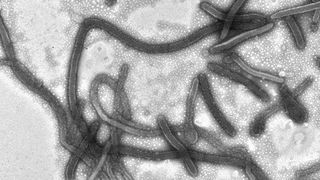

Wirkungsweise von Ebola-Impfstoff-Kandidat genauer untersucht